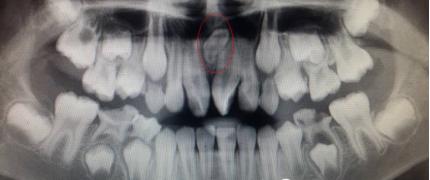

儿童口腔科的医生经过专科查体并配合X线检查,发现是孩子的两颗新长门牙之间有一颗多生牙在作怪,这让李奶奶更紧张了。

临床上发现或有多生牙时,需要拍摄X线片来明确诊断,如牙齿根尖片、全口曲面断层片或CBCT等,确定多生牙的数目和位置。为了减少多生牙对恒牙和恒牙列的影响,应尽早发现,及时处理。已经萌出的多生牙应及时拔除,以有利于邻近恒牙的顺利萌出并减少恒牙的错位。若萌出的多生牙形态与正常牙相似或牙根有足够的长度,而相邻的正常牙齿有牙根吸收、牙根弯曲等问题,可以综合考虑全牙列的情况后拔除相对较差的正常牙而保留多生牙。针对埋伏的多生牙,如果影响恒牙的发育、萌出及排列,在不损伤恒牙胚的情况下应尽早拔除,若不影响恒牙胚发育和萌出,则可等到恒牙牙根发育完成后再拔除。埋伏的多生牙拔除术后还要关注定期复查。